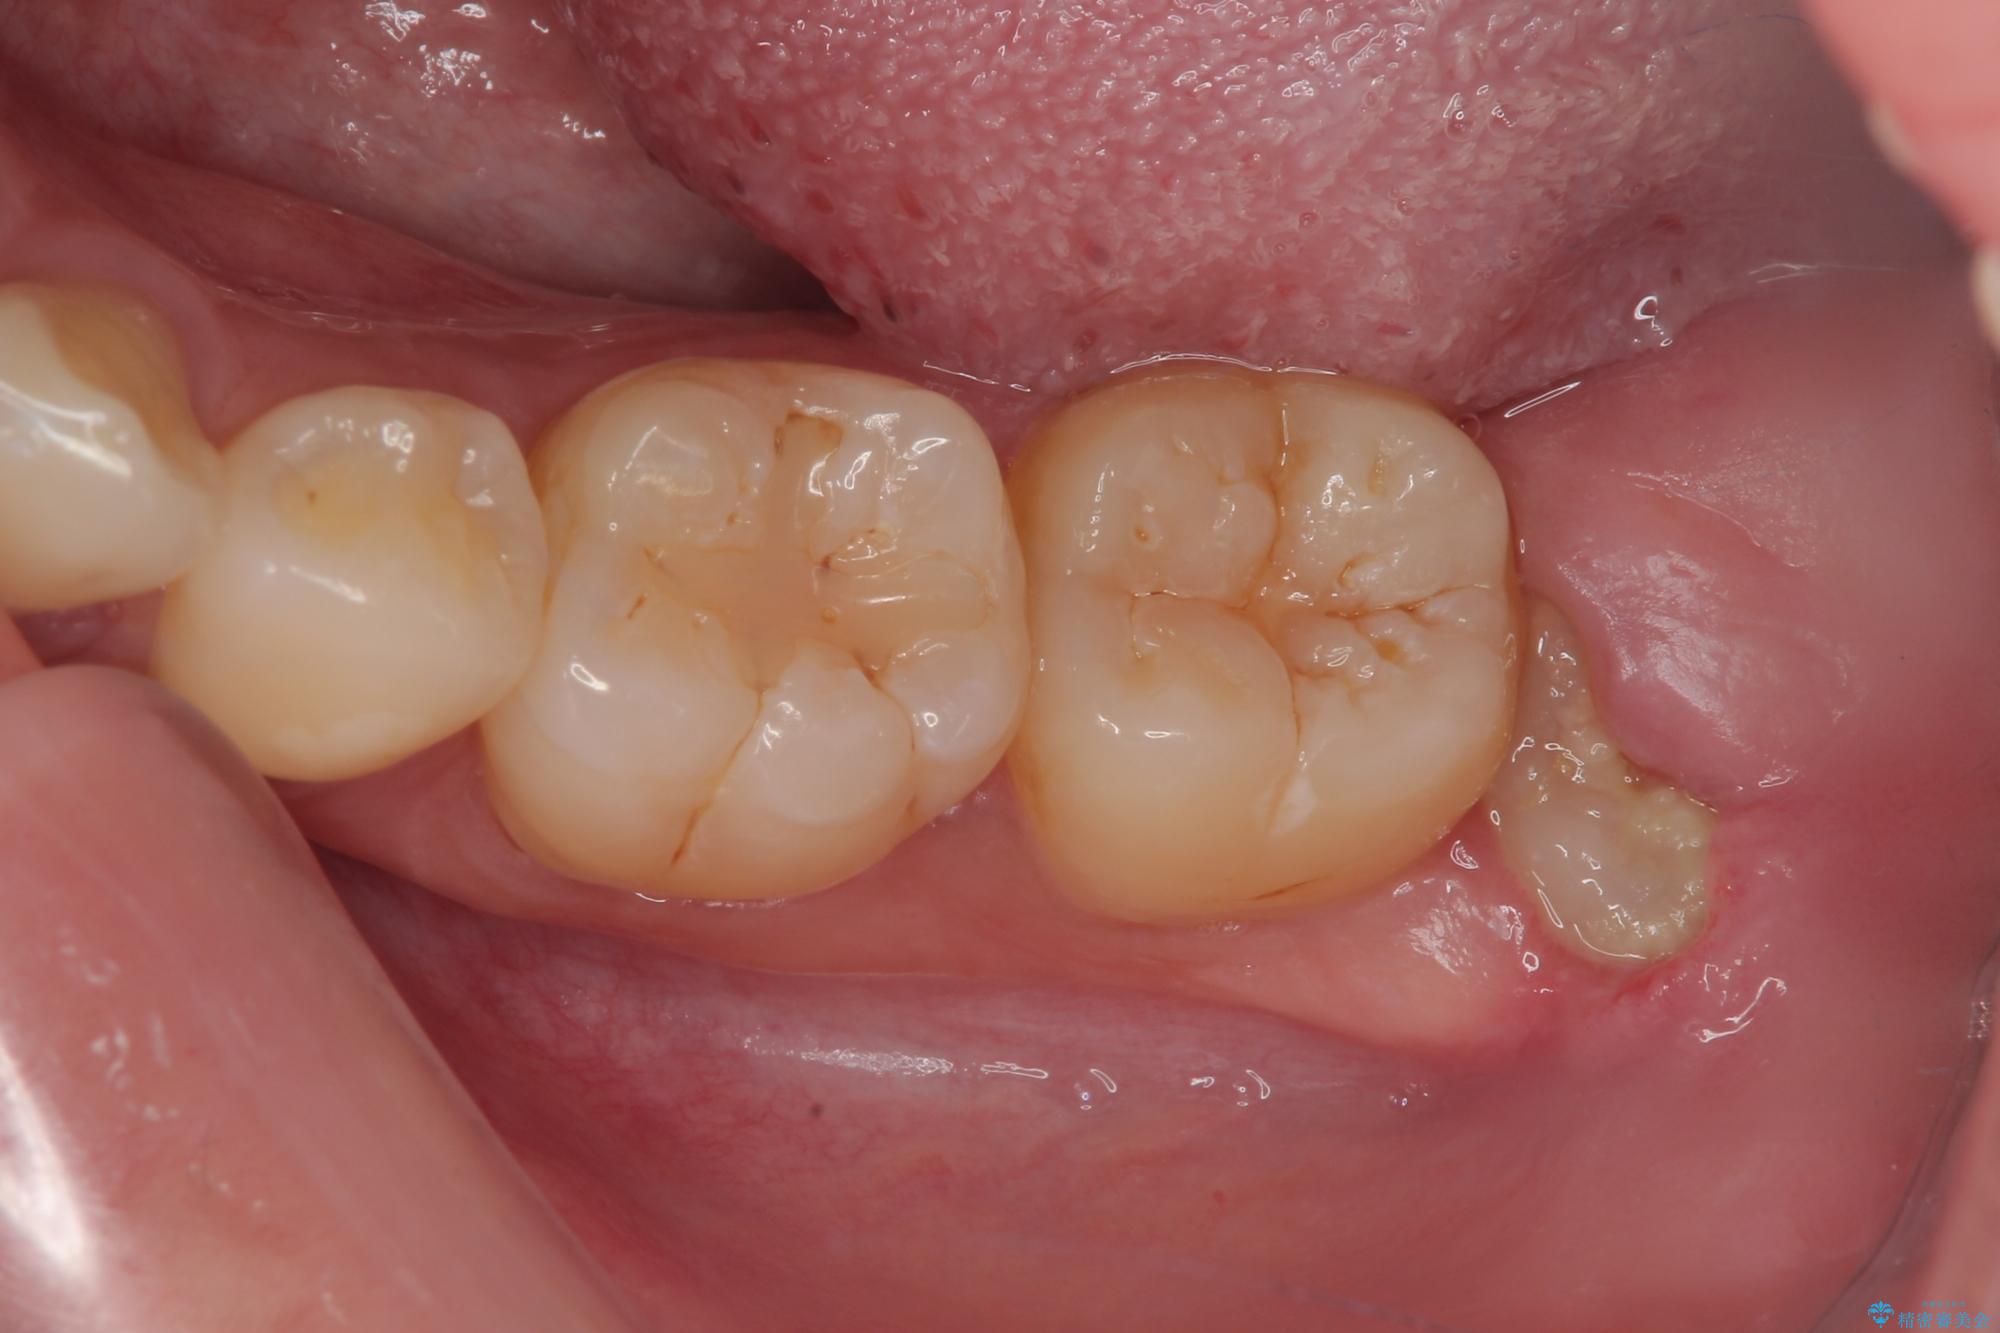

- 親知らずを抜きたいとのことで来院された患者様です。

CTで神経の位置などを確認し、抜歯術を行いました。

しっかり麻酔が効いたことを確認してから安全に抜歯を行いました。